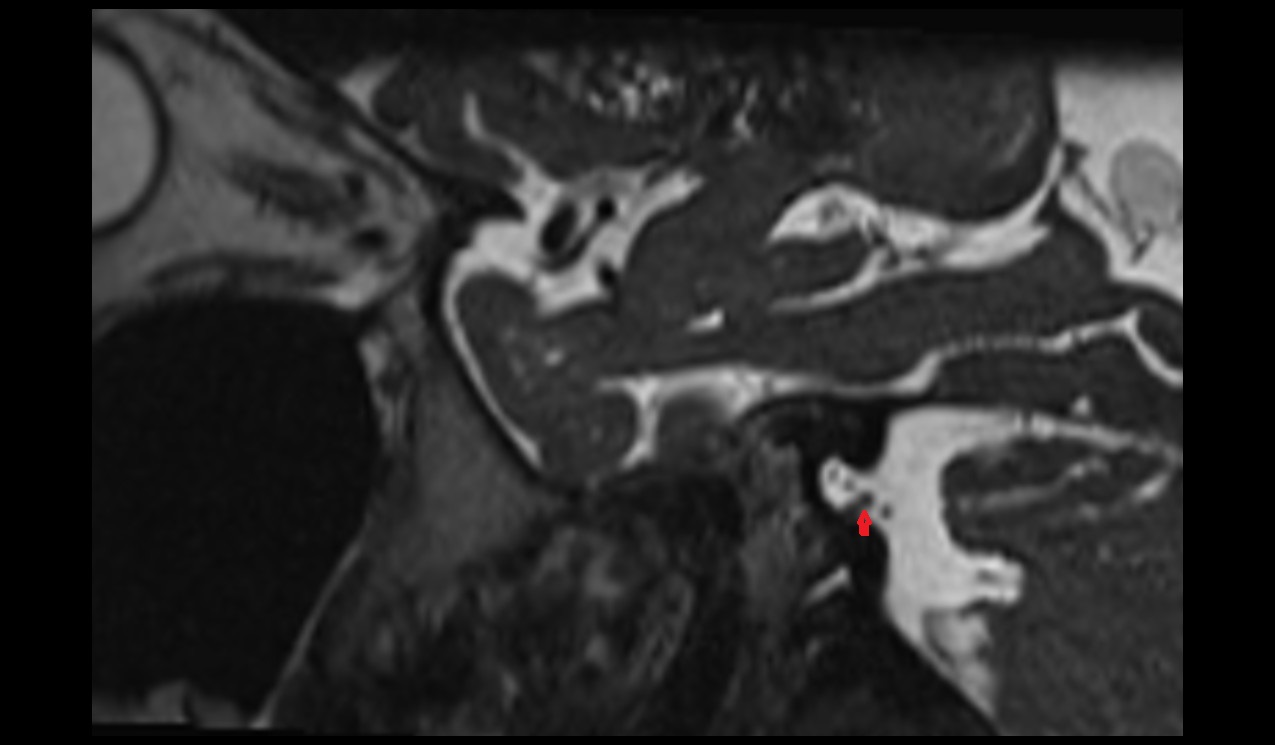

- Articular disc of temporomandibular joint

- Intermediate zone of articular disc

- Superior retrodiscal layer

- Temporomandibular joint

- Mandibular condyle

- Mandibular fossa